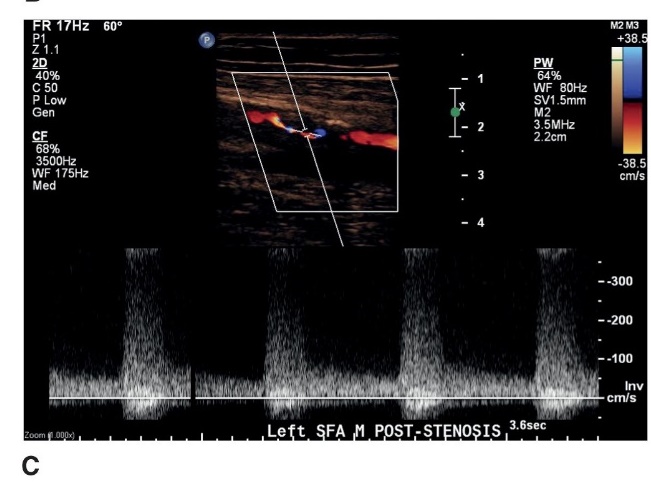

a doppler waveform distal to a stenosis documenting poststenotic turbulence

what does this image represent